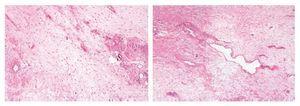

Figura 4. La proliferación neoplásica muestra áreas mixoides hipocelulares alternando con otras de mayor densidad celular con infiltrado inflamatorio mixto y vasos curvilíneos hialinizados.